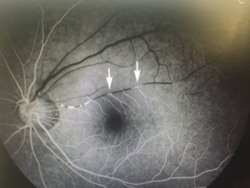

Mù mắt sau tiêm chất làm đẹp

Đã có gần 100 trường hợp trên toàn cầu bị biến chứng mù mắt, đột quỵ sau làm đẹp bằng tiêm chất làm đầy và riêng tại Bệnh viện Nhân Dân 115 TP HCM ghi nhận 3 trường hợp.

Tiêm filler không đảm bảo: Cảnh báo biến chứng nguy hiểm

Thông tin từ Bệnh viện Đại học Y Hà Nội cho biết, bệnh viện vừa tiếp nhận bệnh nhân nữ (25 tuổi, ở Hà Nội) nhập viện trong tình trạng mất thị lực mắt trái.